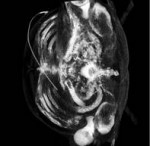

Halbautomatische Segmentierung der knöchernen Strukturen des Kniegelenks in MRT Aufnahmen

Zuverlässige Segmentierung ist eine der wichtigsten und zugleich komplexesten Aufgaben in der modernen Volumen Analyse. Besonders im Bereich der Medizin sind bildgebende Verfahren heute ein integraler Bestandteil des klinischen Alltags geworden, was zur Folge hat das ein hoher Prozentsatz der Arbeitszeit auf die Nachbearbeitung bzw. Strukturfindung aufgewendet werden muss. Hier setzen (teil-) automatisierte, modellbasierte Verfahren an. Eine prominente Klasse der modellbasierten Segmentierungsverfahren ist der "Deformable Model" Ansatz. Grundidee ist die Verwendung eines initiales Modells, üblicherweise durch ein 3D Netz repräsentiert, welches in einem iterativen Verfahren an die zu findende Kontur angepasst wird und sich in jedem Schritt ausbreitet oder schrumpft, vergleichbar mit einem Ballon in den (lokal) Luft hingepumpt oder abgelassen wird. Ziel dieser Arbeit ist es, unter Verwendung des am Welfenlab entwickelte YaDiV Deformable Model Framework (YDMF) angepasste Modelle für die knöchernen Strukturen im Bereich des menschlichen Kniegelenks (Patella, Femur, Tibia) zu entwickeln. Als Volumendaten werden MRT-Aufnahmen zum Einsatz kommen, was eine zusätzliche Herausforderung an das Modell darstellt, da die Differenzierung von knöchernen Strukturen durch Weichgewebe in MRT-Aufnahmen erschwert wird.

Als erster Schritt soll ein Modell für die Patella entwickelt werden, welches mit anatomischen Landmarken versehen wird und durch eine lokal und global angepassten Expansions- bzw. Erosionskraft die Strukturfindung ermöglicht. Das Modell soll mit einer geringen Auswahl an Datensätzten trainiert und anschließend durch die Anwendung in neuen Aufnahmen evaluiert werden. Die gewonnen Erkenntnisse sollen dann für die Modellierung der Femur bzw. Tibia Modelle genutzt werden, bei denen die zusätzliche Herausforderung besteht, das hier oft nur eine Teilabdeckung im Aufnahmebereich besteht. Betreuer: Karl-Ingo Friese November 2011